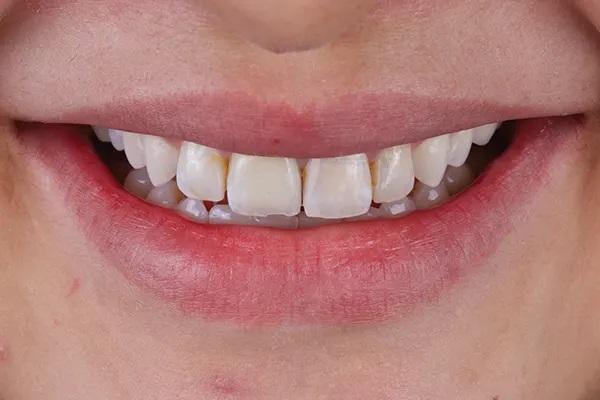

Пациентка 33 лет обратилась с жалобами на дефект прямой реставрации в переднем отделе выполненной из специальной смолы, имеющаяся у нее конструкция с опорой на имплантаты также имела дефект, а именно скол керамики по режущему краю резца и соседние зубы аномального размера (Фото 1 - Фото 3). В ее истории болезни не было выявлено противопоказаний к стоматологическому лечению. В 2015 году для восстановления целостности зубного ряда ей был установлен имплантат в области зуба 1.1., и рентгенологическое исследование показало, что имплантат хорошо сросся с костью. Глубина зондирования пародонта и тканей, окружающих имплантат, составляла от 3 до 4 мм, без признаков активного воспаления. У пациентки был хороший уровень гигиены полости рта.

Фото 2. Вид улыбки пациентки до начала лечения.